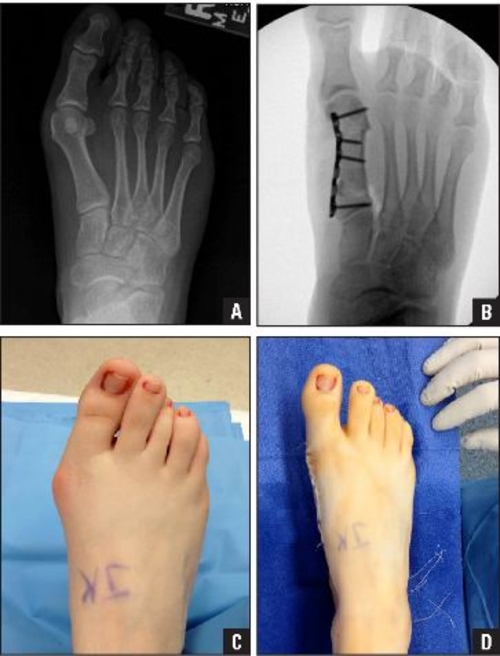

Orthopedics Bone Grafts And Club Foot Dr Omer Barawe